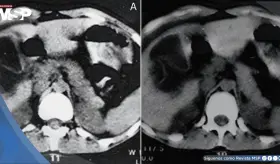

Paciente presenta ruptura intraperitoneal de quiste parasitario después de presión abdominal súbita, manifestando dolor intenso en hipocondrio derecho con irradiación al hombro.